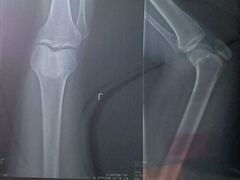

• 广州中医药大学第一附属医院(总院)

• -广州中医药大学第一附属医院(总院)